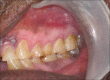

Peripheral ossifying fibroma (POF) is one of the inflammatory reactive hyperplasia of gingiva. It represents a separate clinical entity rather than a transitional form of pyogenic granuloma and shares unique clinical characteristics and diverse histopathological features. We present a case of POF in a 65-year-old male patient in the posterior maxillary gingiva, the clinical presentation of which differs from the usual presentation. Differential diagnosis and some interesting facts of POF are discussed.